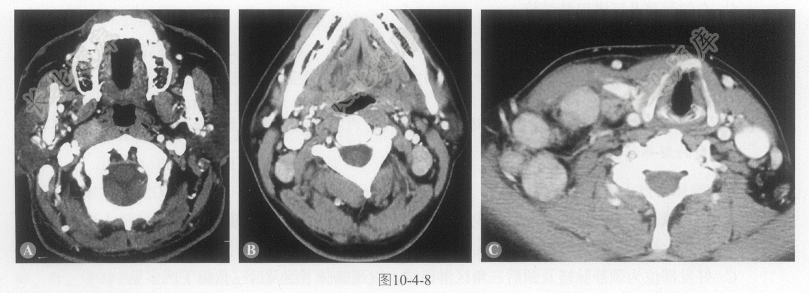

- 多项选择题1.行增强CT扫描,如图10-4-8,根据图中显示,肿物分布于哪些淋巴结区域:

A、右侧咽后组

B、右颈部Ⅰ区

C、右颈部Ⅱ~Ⅳ区

D、右颈部Ⅴ区

E、右颈部Ⅵ区